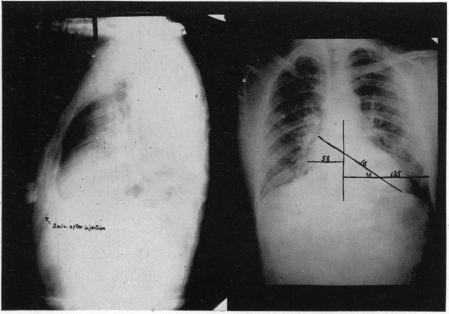

CONGENITAL ARTERIOVENOUS ANGIOMA OF THE ARM: METASTASES ELEVEN YEARS AFTER AMPUTATION.

Ann Surg. 1940 Jun;111(6):1021-45. doi: 10.1097/00000658-194006000-00009.